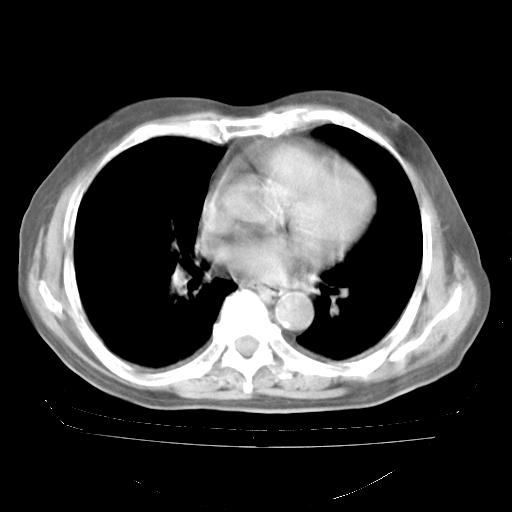

4月28日肺部CT——再次出现类似去年5月9日——透光度降低,“间质性”改变。

4月28日肺部CT——再次出现类似去年5月9日——磨玻璃样、间有“粟粒样”改变。